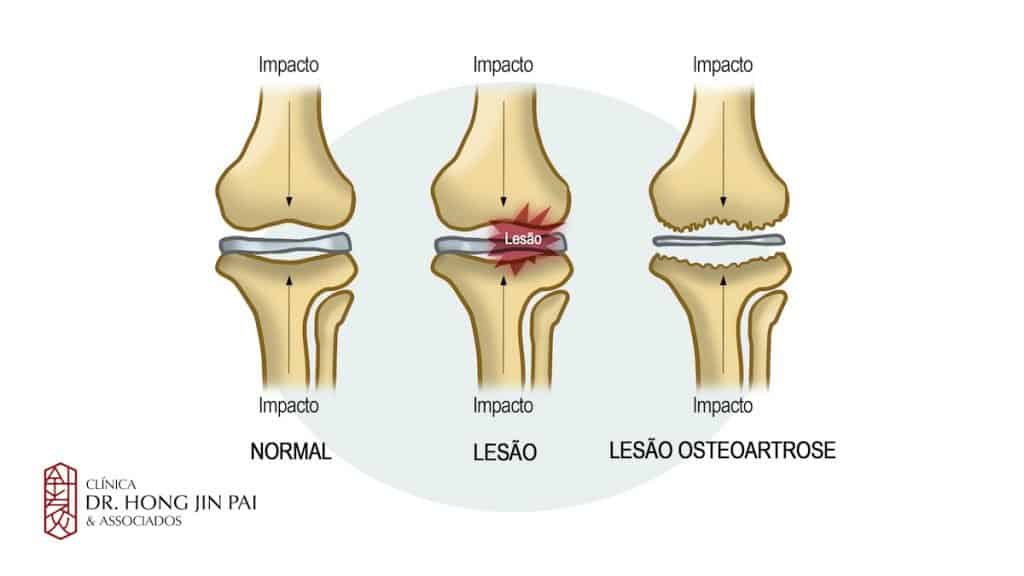

A osteoartrose é uma doença degenerativa causada por múltiplas lesões nas articulações. Nela, a cartilagem que reveste as extremidades dos ossos, responsável por permitir movimentos suaves e sem atrito, vai se desgastando. Com o tempo, a superfície se torna áspera e irregular, aumentando a fricção até que os ossos passem a se mover em contato direto. Esse processo pode provocar dor, inflamação, rigidez e até limitar os movimentos.

Embora possa atingir qualquer articulação, a doença é mais comum nas mãos, joelhos, quadris, ombros e coluna vertebral. No Brasil, 30% a 40% das consultas em ambulatórios de reumatologia estão relacionadas à condição, segundo a Sociedade Brasileira de Reumatologia (SBR). Também conhecida como artrite ou artrose, a doença figura entre as principais causas de afastamento do trabalho, sendo responsável por 7,5% dos casos registrados.

Como confirma o ortopedista Guilherme, os sintomas podem passar despercebidos. “No início, aparece apenas durante esforços maiores e, com a evolução do quadro, pode estar presente até mesmo em repouso”.

A dor no quadril nem sempre é fácil de reconhecer. Muitas pessoas confundem os sinais iniciais com dor lombar ou muscular, o que pode atrasar o diagnóstico da osteoartrose. Como explica o ortopedista Guilherme Falótico, a dor típica da doença aparece na região inguinal (virilha) e se manifesta durante movimentos de rotação do quadril ou esforços maiores. “No início, o paciente pode sentir desconforto apenas durante a atividade física, mas com a evolução do quadro a dor pode aparecer até em repouso”, esclarece.

A distinção é importante: a dor muscular geralmente surge como fisgada ou após esforço, e a lombar acomete a região posterior, piorando ao dobrar o tronco para frente. Já a dor articular da osteoartrose é profunda e localizada na virilha.

Os fatores de risco incluem predisposição genética, alterações mecânicas na anatomia do quadril e condições metabólicas que favorecem inflamação articular. A doença é mais comum em pessoas acima dos 50 anos e atinge mais mulheres, mas casos em idades mais jovens vêm crescendo.

O impacto da osteoartrose vai além da dor: limitações de movimentos simples, como cortar as unhas, calçar sapatos ou vestir meias, são comuns, e o impacto emocional pode aumentar a percepção de dor e frustração. Por isso, exercícios de baixo impacto, fortalecimento muscular, alimentação saudável e manutenção do peso são aliados importantes no controle da doença.